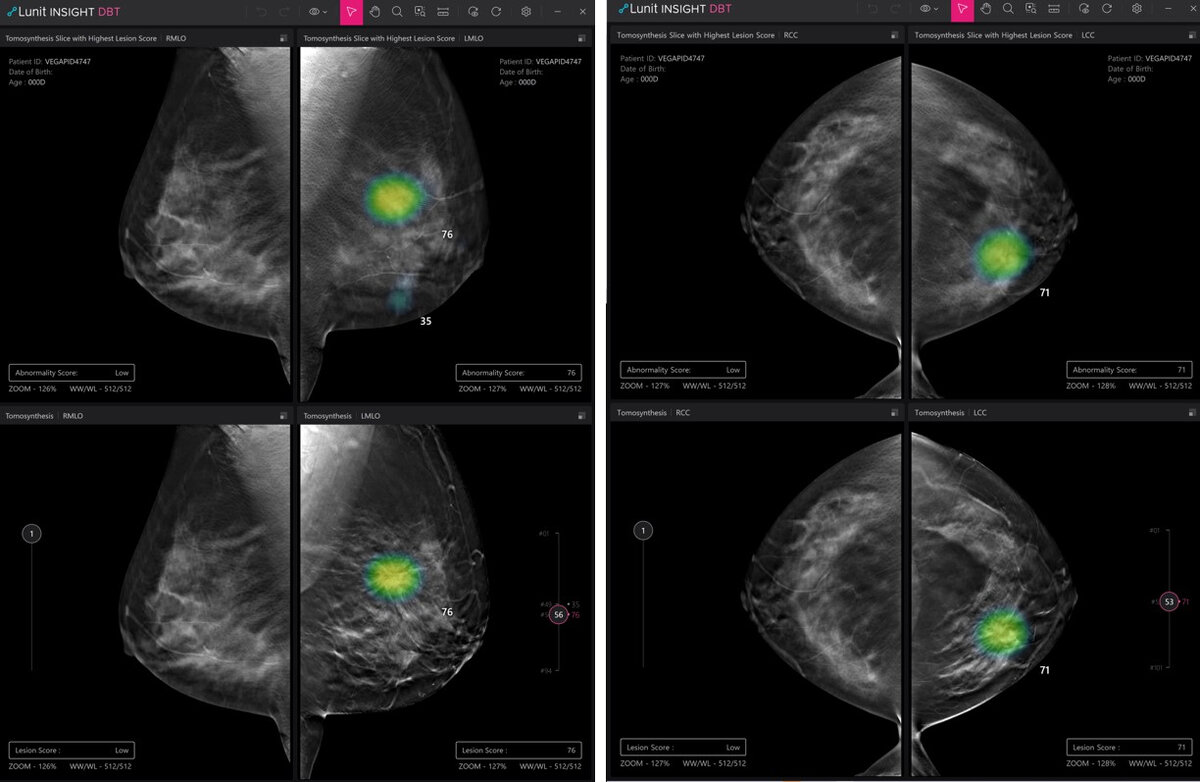

Демонстрационные фотографии цифрового томосинтеза молочной железы Lunit Insight (Lunit)

Решение, получившее название «Цифровой томосинтез молочной железы Lunit Insight (Lunit Insight Digital Breast Tomosynthesis)», представляет собой программное решение на основе искусственного интеллекта, помогающее выявлять подозрительные очаги с помощью 3D-маммограмм.